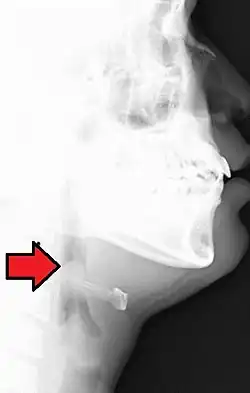

Vue latérale en radiographie révélant le "signe du pouce" qui indique un gonflement de l'épiglotte, évocateur d'une épiglottite aiguë.

L'épiglottite est un type de laryngite pouvant constituer une urgence vitale chez l'enfant et consistant en un œdème de l'épiglotte obstruant les voies aériennes supérieures.